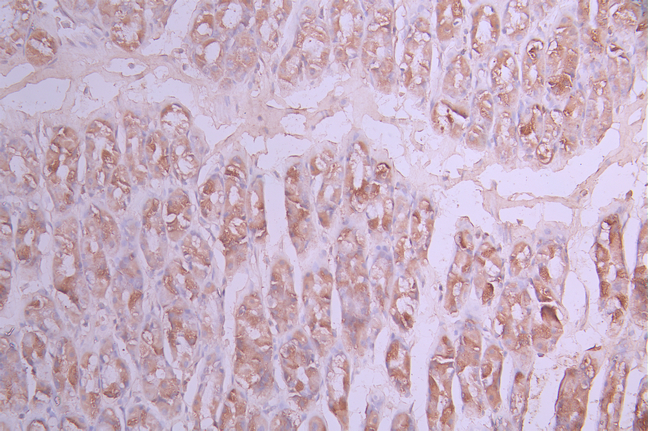

IHC image of CSB-RA244970A0HU diluted at 1:100 and staining in paraffin-embedded human breast cancer performed on a Leica BondTM system. After dewaxing and hydration, antigen retrieval was mediated by high pressure in a citrate buffer (pH 6.0). Section was blocked with 10% normal goat serum 30min at RT. Then primary antibody (1% BSA) was incubated at 4°C overnight. The primary is detected by a Goat anti-rabbit polymer IgG labeled by HRP and visualized using 0.05% DAB.